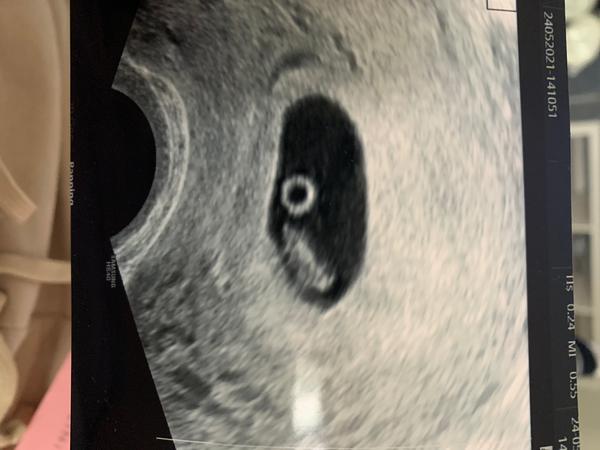

Ahoj holky dnes jsem byla na kontrole a doktorka rekla ze už bije srdicko.. naštěstí, protože když jsme byla v 6+1 ještě nebylo.. a zacala jsem hodně malo špinit takže jsem radsi přišla a bylo tam 💙 jen mi vrtá hlavou proč měřila ten plod vpravo a co je teda to vlevo kulatý?

@flowerstone jojo přesně tak tělísko na vyživovací plodu, než bude placenta

@flowerstone žloutkový váček

@flowerstone to je zloutkovi váček vizivuje miminko

@flowerstone Já myslím, ze žluté tělísko z kterého je embryo vyživované a zaniká se vznikem placenty...taky jsem ho mela takhle hezky vidět